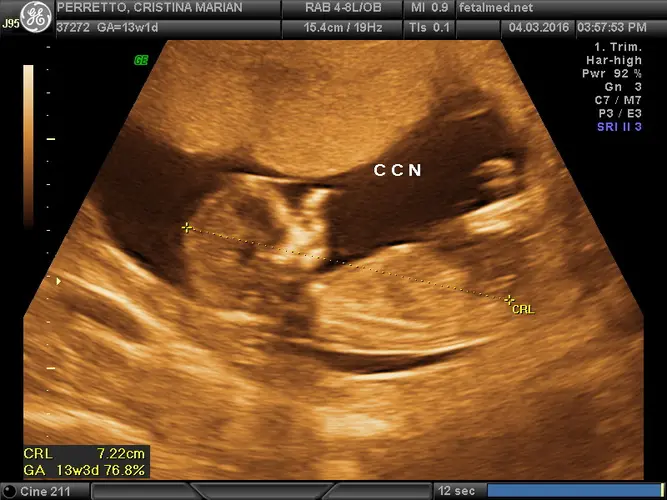

A 13ª semana representa praticamente o final da janela para realizar o morfológico de primeiro trimestre (translucência nucal). Este exame é fundamental para avaliar o risco de alterações cromossômicas, como a síndrome de Down, e deve ser realizado idealmente entre 11 e 14 semanas de gestação.

Se você ainda não realizou este exame, é importante agendar com urgência, pois após a 14ª semana a avaliação da translucência nucal perde sua precisão diagnóstica. O exame também permite uma avaliação detalhada da anatomia fetal precoce e confirmação mais precisa da idade gestacional.